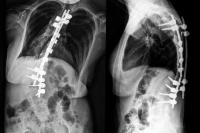

Side-by-side spinal X-rays showing metal rods along the spine.

An alternative to traditional growing rods, which require 8–10 lengthening surgeries during a child's growing years, the MAGEC device allows surgeons to straighten and correct the spine gradually and noninvasively.

Candidates for the MAGEC device undergo an initial surgery to implant an adjustable magnetized growing rod. Once the rod is implanted, it can be lengthened externally with a hand-held magnetized device, which eventually straightens the spine.